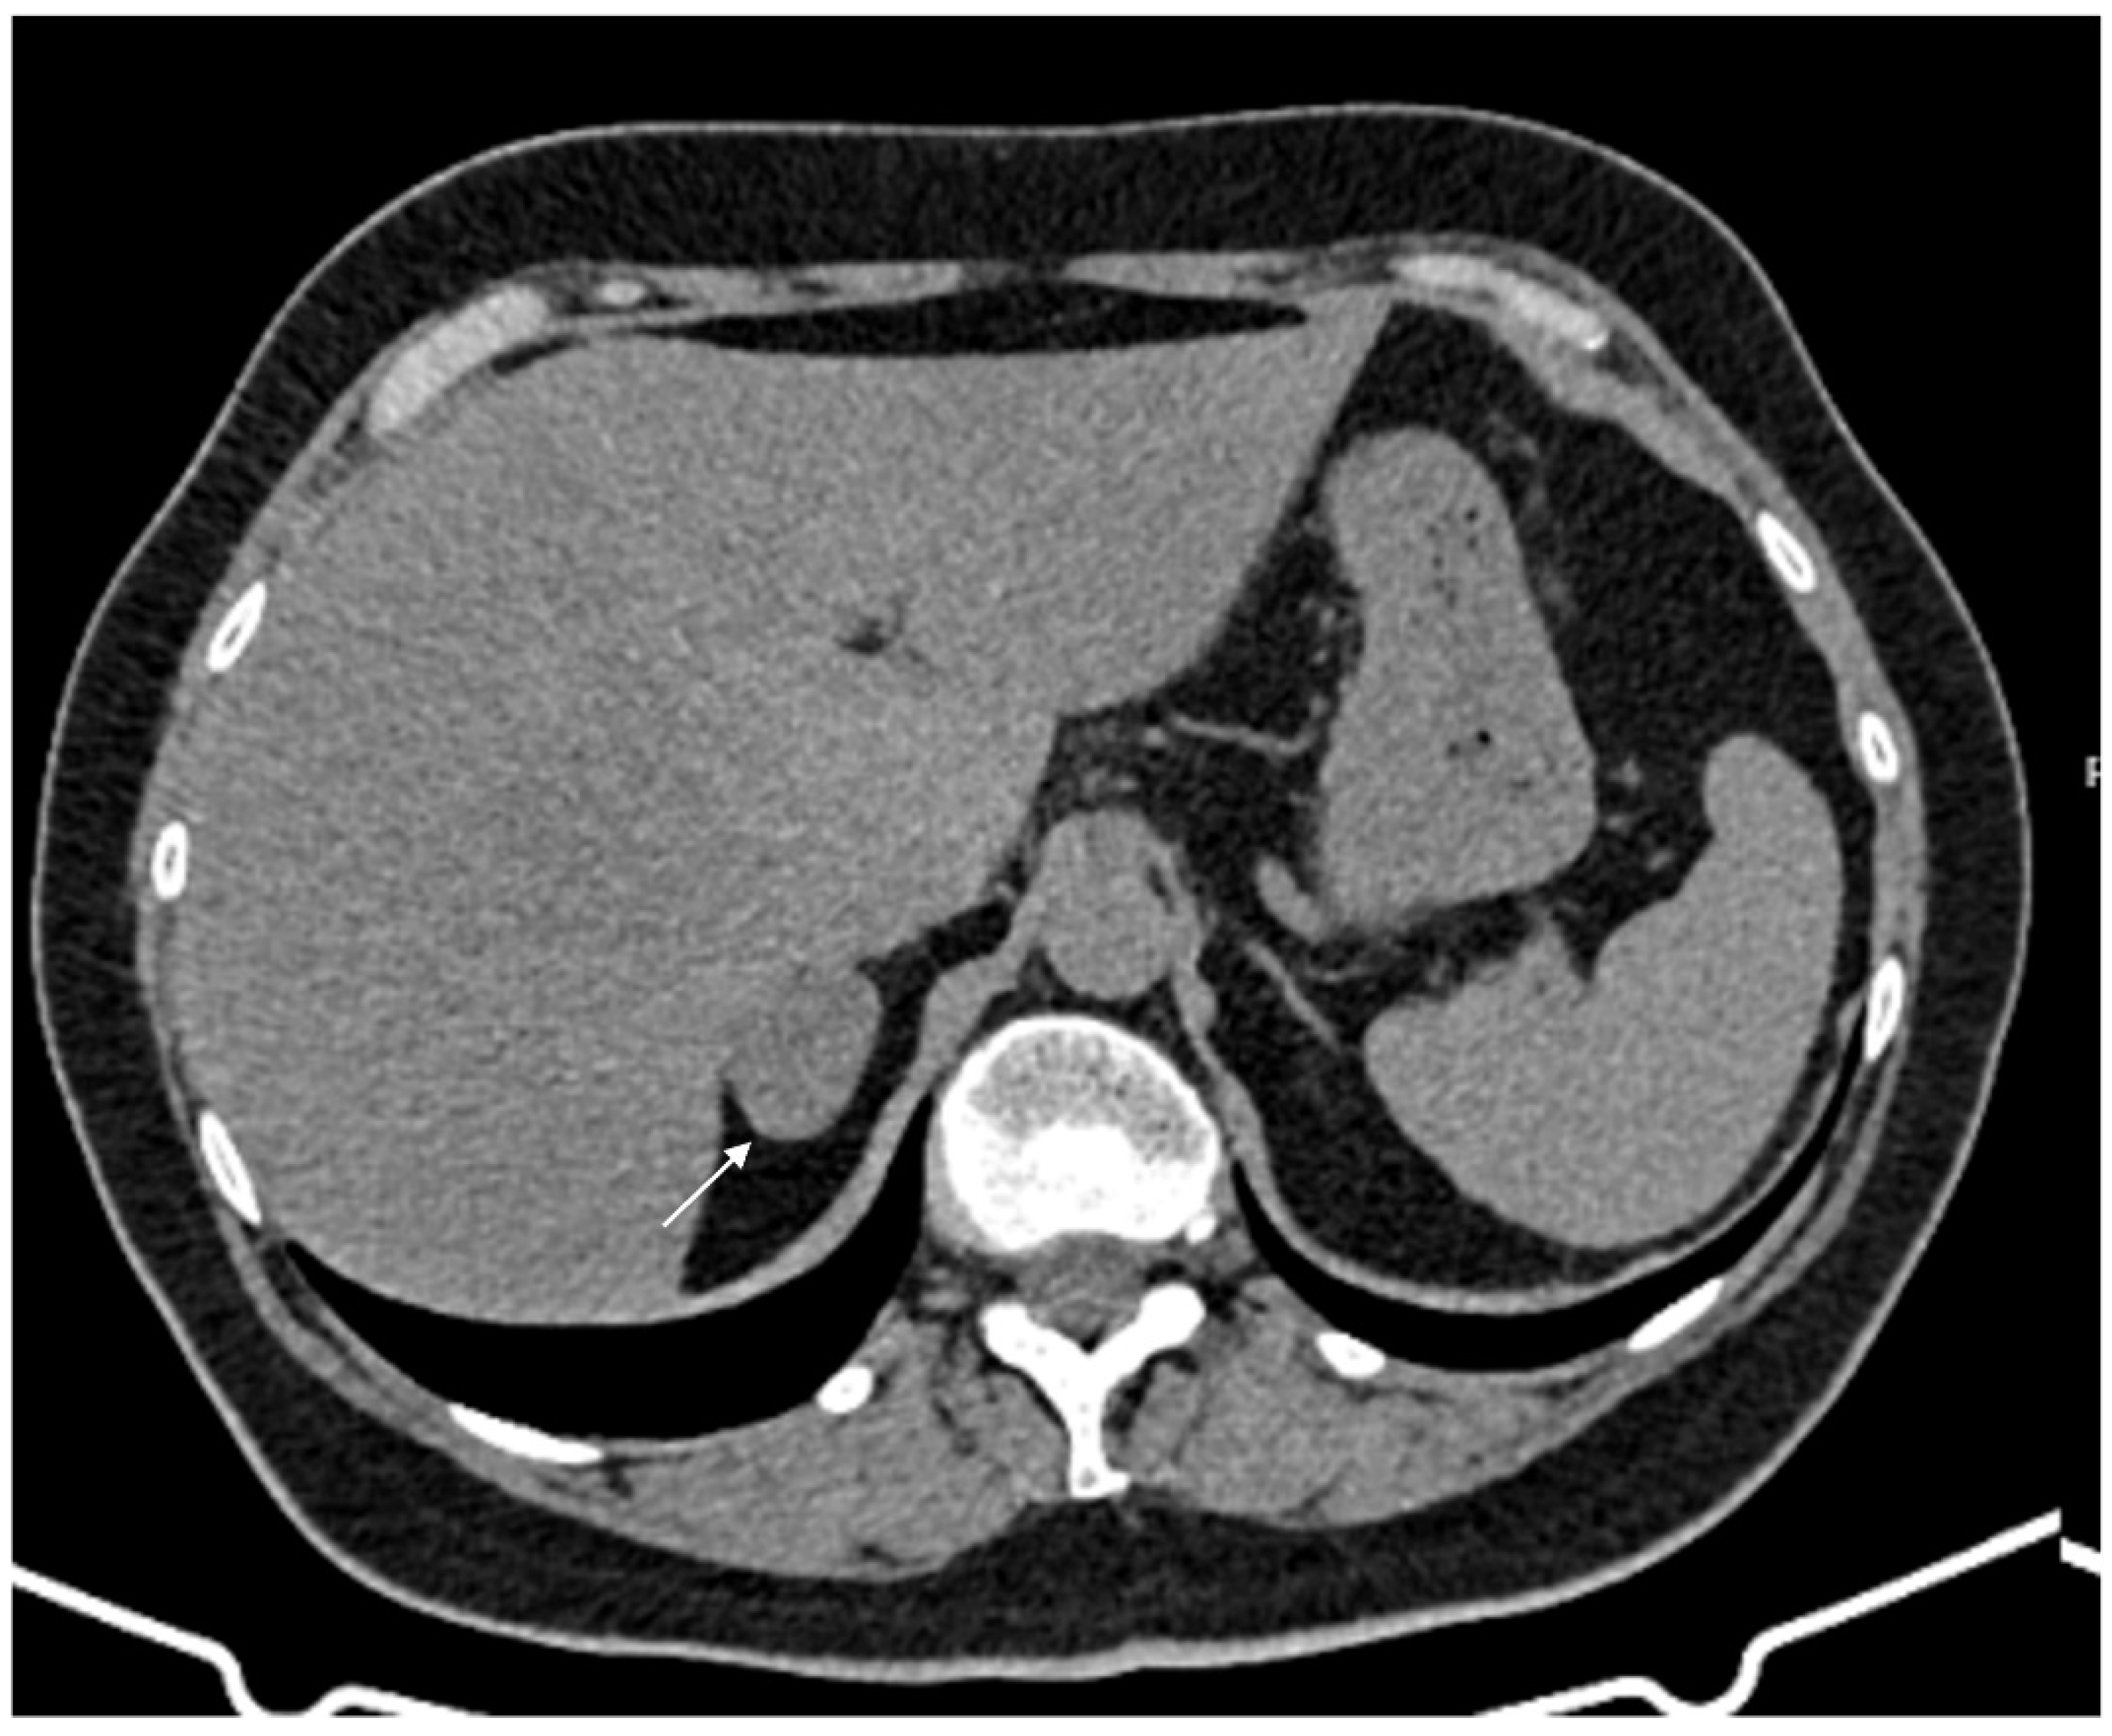

Figure 1.

60-year-old woman with adrenal adenoma. Accidental CT finding of a right adrenal mass (arrow) of approximately 3 cm, homogeneous with clear margins and density values lower than 10 HU.

Figure 2.

74-year-old male patient. Following an MRI of the digestive tract incidental finding of bilateral adrenal secondary hyperplasia. Both enlarged limbs adrenal glands > 10 mm thick with multiple nodularity hypodense on non-contrast CT (arrows).